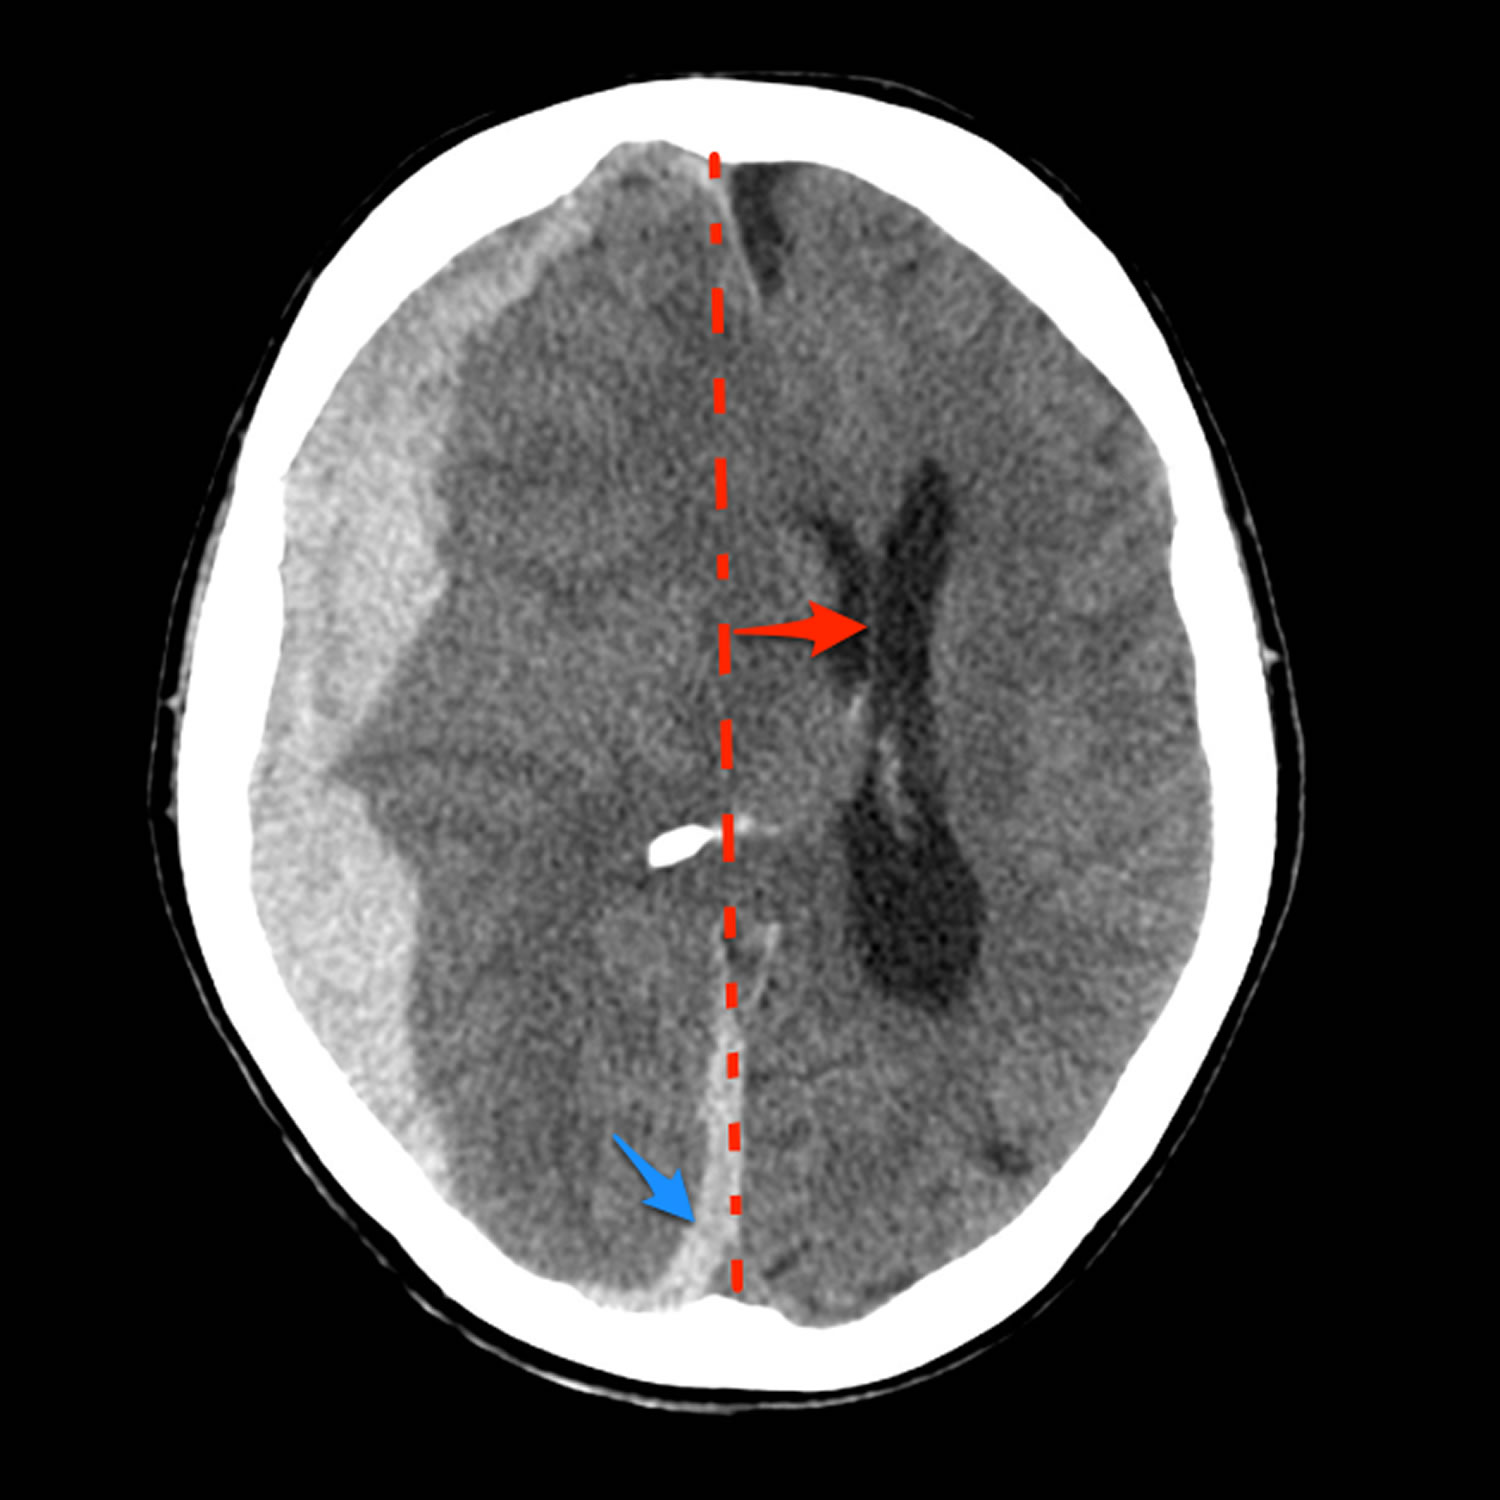

TitleMidline Catheter